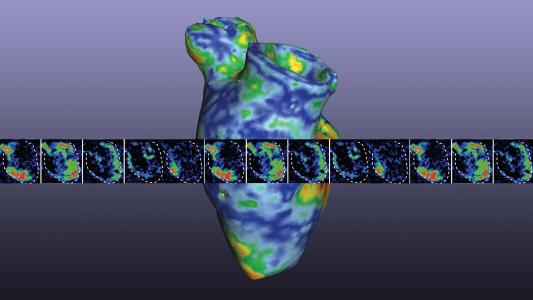

Scientists 3D print a heart pump that can beat on its own

Scientists 3D print a heart pump capable of beating on its own — and the organoid could have a big impact on heart research.